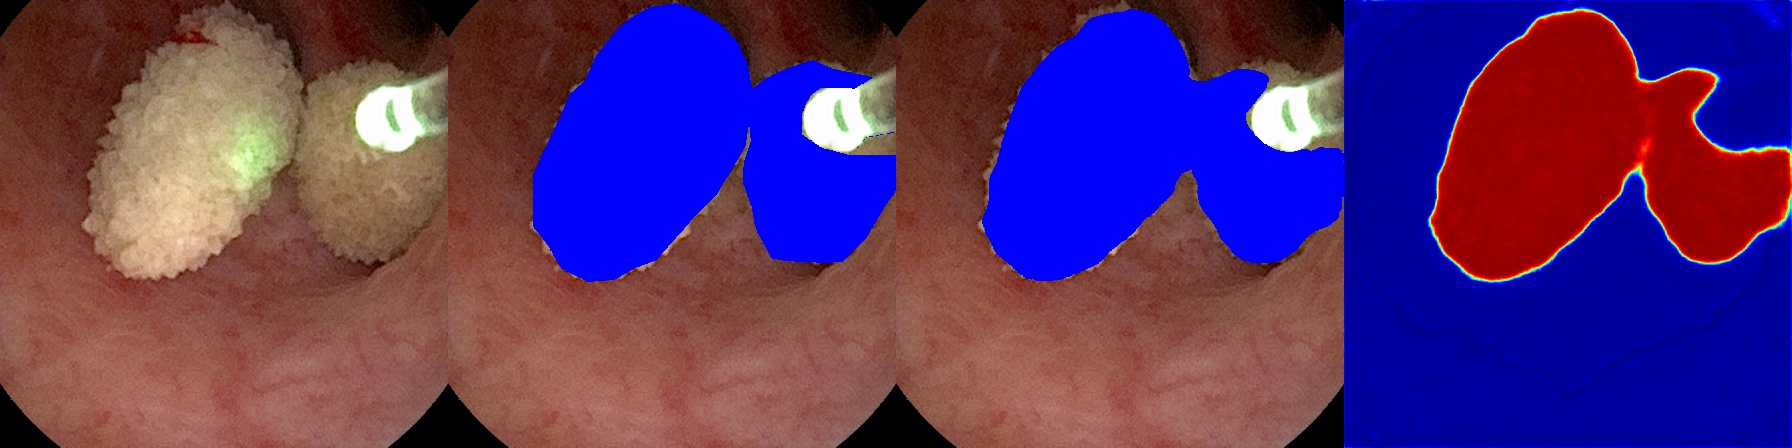

We developed a script for processing video feeds and making predictions using our trained models. The script provided sequential frames to the model and ran slightly faster than the duration of each video being processed, which is better than 30 FPS. Videos were separated and reconstructed using OpenCV’s video processing pipeline. Together with the model input and the predicted annotation, we reconstructed the video, containing a model input, its predicted annotation, and the corresponding probability map for side-by-side comparison, from the frames sequentially passed through the model. For testing, ground truth images were also available and included in the comparison image. Figure 4 shows an example of a frame used for side-by-side comparison with its ground truth, prediction, and probability shown as a heat map overlay. The GPU hardware used was an NVIDIA RTX 2080 Ti.

Refer to caption

Figure 4: Sample frame from the side-by-side video reconstruction of the input, ground truth, automated prediction with U-Net++, and heat map (left to right). The heat map is the raw probability output per pixel whereas the predicted segmentation is the pixels with probabilities \geq 0.5. The model was able to compute this output at 30 FPS.